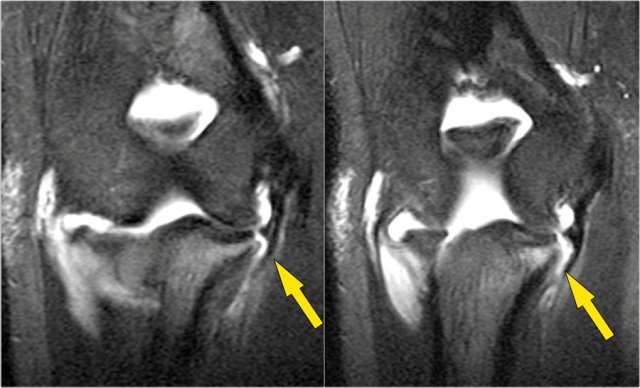

Here a different patient.

Notice that it is a young patient, because the physis is still open.

There is a large osteochondral lesion in the lateral trochlea (yellow arrows).

Notice the edema in the subchondral bone (red arrow).

The cartilage is still intact.